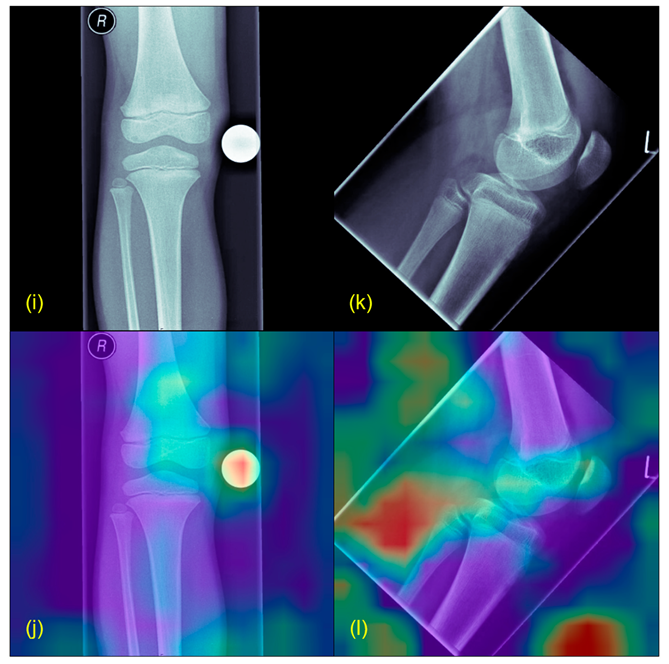

2.5. Plausibility